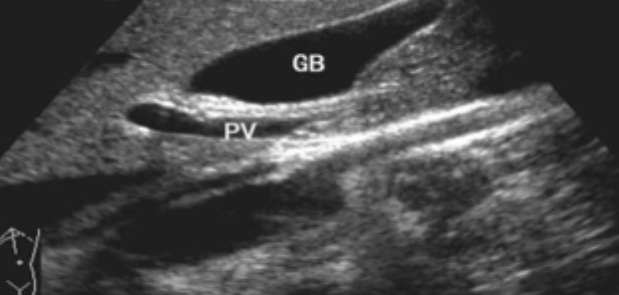

一、正常膽囊超聲圖像有的時(shí)候經(jīng)常發(fā)現(xiàn)檢查不到膽囊,其實(shí)有幾種可能性,檢查人員的技術(shù)不過(guò)關(guān)沒(méi)發(fā)現(xiàn)膽囊,就要找上級(jí)醫(yī)生會(huì)診,如果還是沒(méi)找到的話就不是技術(shù)問(wèn)題。結(jié)石或腫瘤充滿膽囊,使其液腔消失,慢性膽囊炎使得膽囊萎縮或膽囊壁肥厚而囊腔消失患者已進(jìn)食,膽囊處于膽汁排空的狀態(tài),膽囊先天性過(guò)小或缺失;膽囊位置極端異常(可能很低或位于左側(cè))膽囊切除術(shù)后(注意詢問(wèn)病史)。